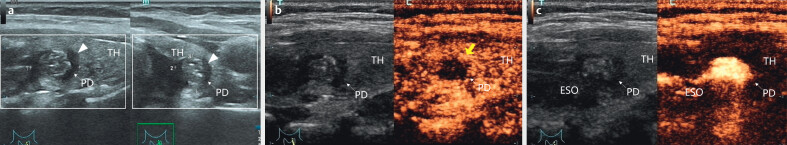

Abstract Image